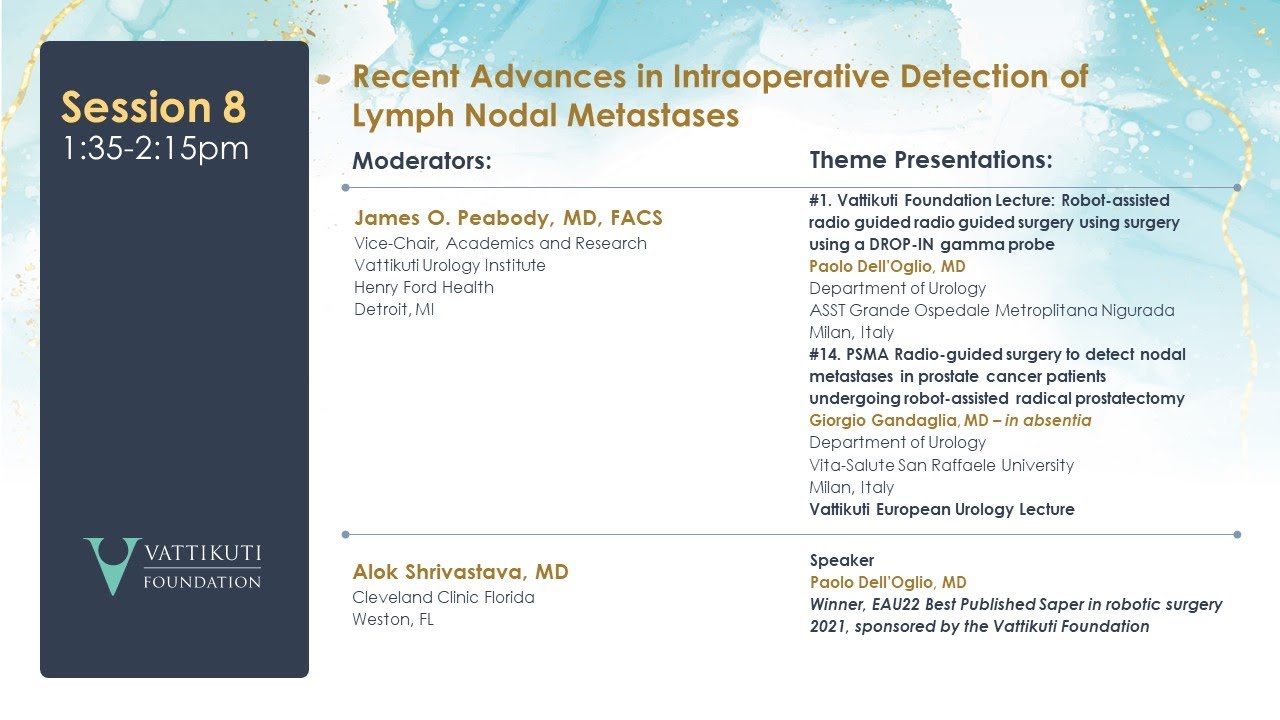

Session 5: Recent Advances in Intraoperative Detection of Nodal Metastases in Prostate Cancer

Session 4: Recent Advances in Intraoperative Detection of Nodal Metastases in Prostate Cancer

Session 3: Recent Advances in Intraoperative Detection of Nodal Metastases in Prostate Cancer

Session 2: Recent Advances in Intraoperative Detection of Nodal Metastases in Prostate Cancer

Session 1: Recent Advances in Intraoperative Detection of Nodal Metastases in Prostate Cancer

Recent Advances in Intraoperative Detection of Nodal Metastases in Prostate Cancer

PSMA Radio Guided Surgery in Primary Prostate Cancer

Robot-assisted radioguided surgery using a DROP-IN gamma probe